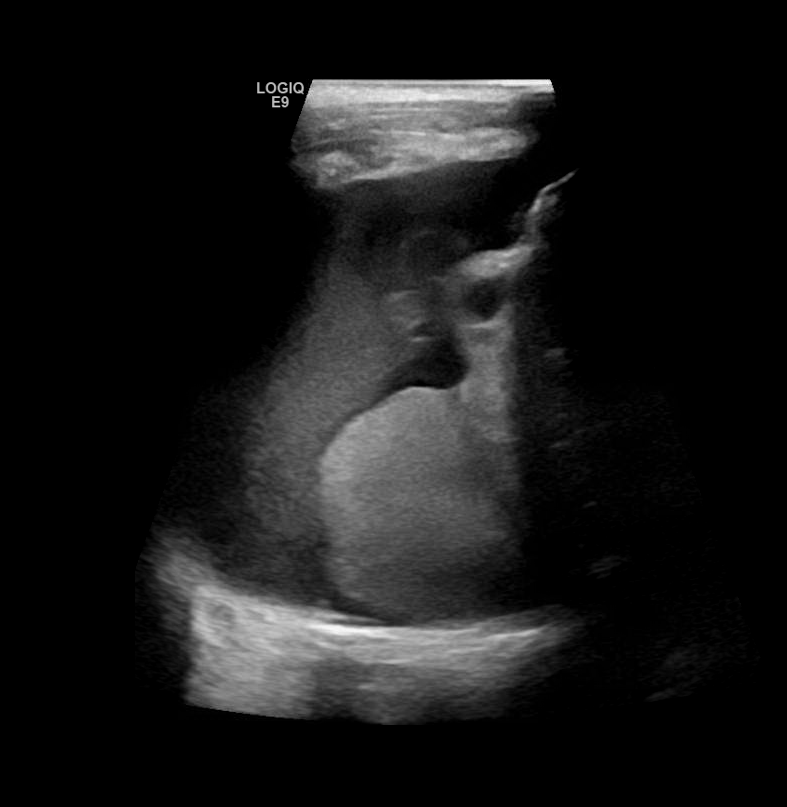

Diaphragmatic Hernia

Congenital diaphragmatic hernia is a defect or hole in the diaphragm that allows abdominal contents to enter the chest cavity. Most cases are diagnosed prenatally. Neonates typically present with respiratory distress acutely after birth. The lung on the affected side is usually hypoplastic.

Right sided hernia with liver and hypoplastic lung